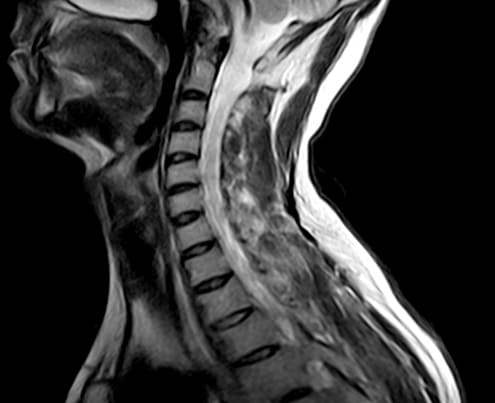

МРТ при шейном остеохондрозе назначается крайне редко, но исследование проблем в грудном отделе чаще всего требует применения этого метода. Его основным преимуществом является то, что на снимках четко видны не только нарушения в структуре скелета, но и патологические процессы в мягких тканях.

Поскольку для хорошей визуализации магнитно-резонансному томографу нужно много клеток с атомами водорода, то ткани с большим содержанием воды лучше всего визуализируются на МРТ снимках. Поэтому МР-томография позвоночника очень хорошо показывает:

- спинной мозг;

- нервные волокна;

- сосудистое русло;

- мягкие ткани (мышцы, сухожилия, связки, межпозвоночные диски).